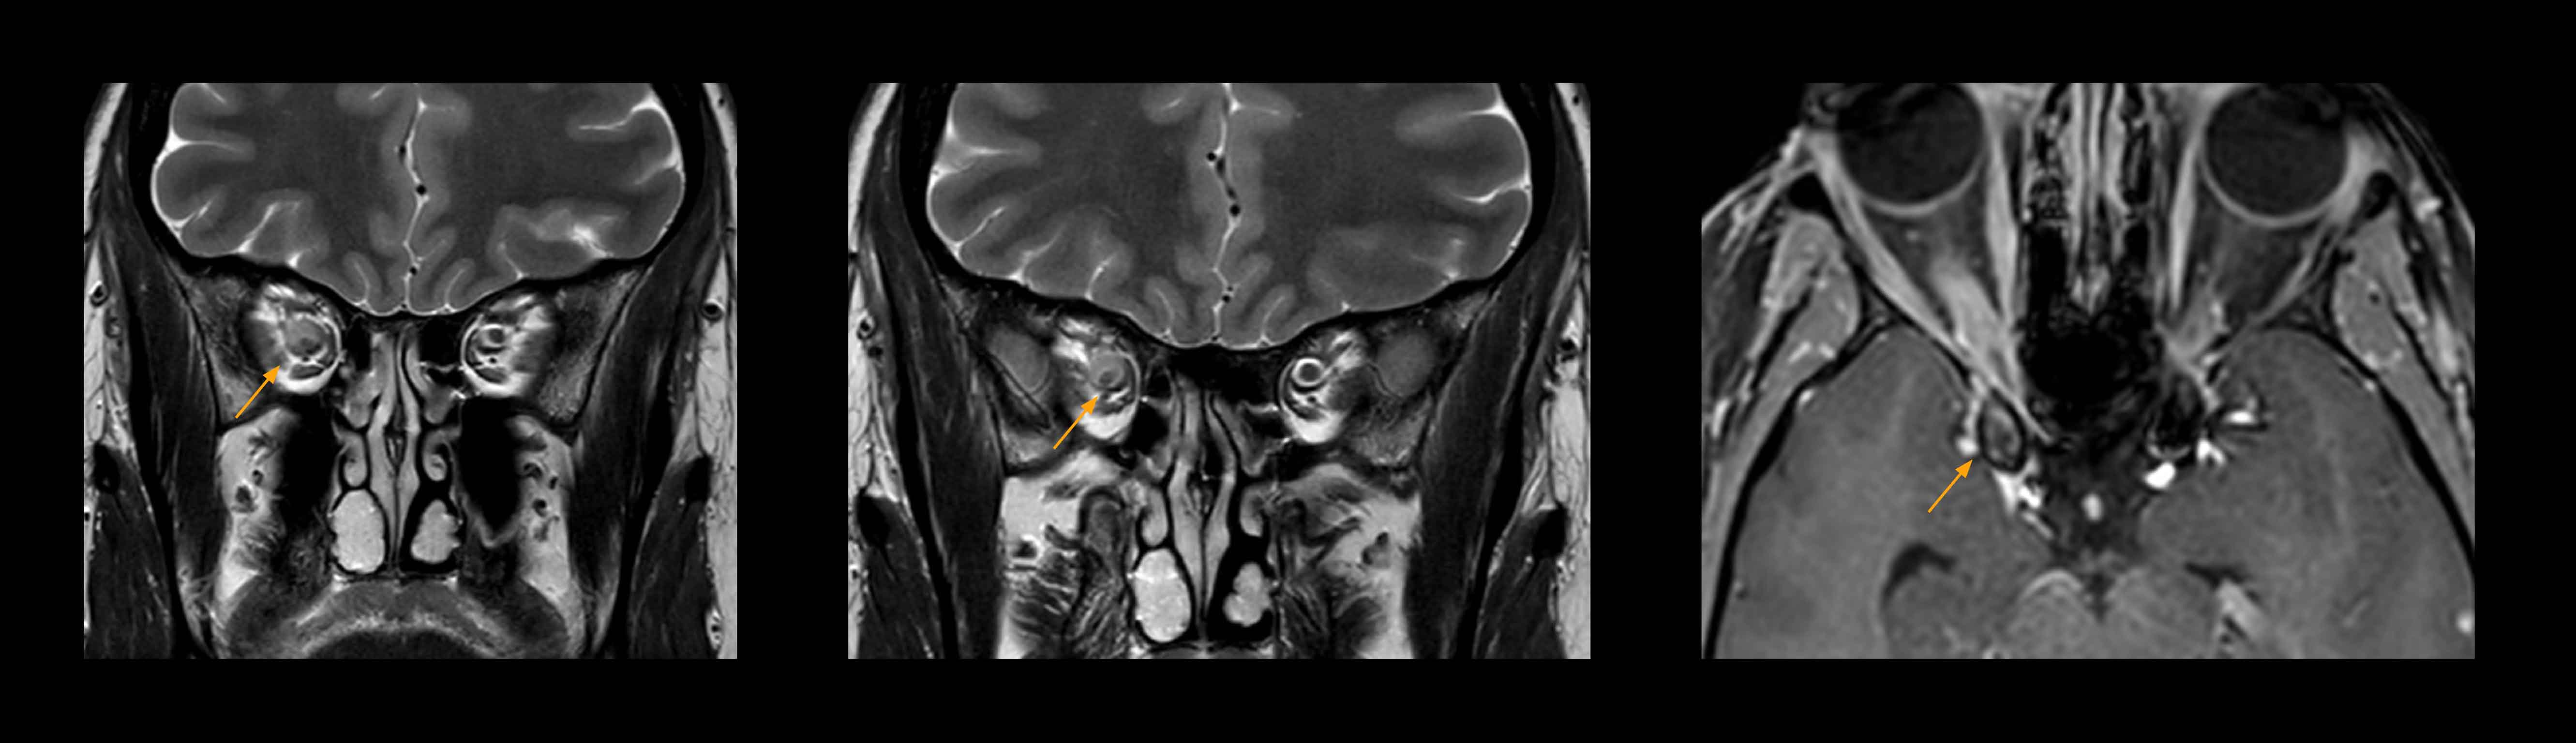

High resolution providing diagnostic confidence

In select cases, the MR 7700 has helped the hospital’s physicians more clearly visualize pathology. “We’re definitely getting the impression that tumors are better delineated with the MR7700,” Dr. Heindel says. “For example, I examined a patient who had been diagnosed in another hospital with possible neuritis of the optic nerve. However, the MR 7700 images allowed me to diagnose it as an optic nerve sheath meningioma, a rare and often misdiagnosed, slowly growing tumor that wascausing the visual disturbances in the patient. The lesion was so well delineated on the high resolution MR 7700 images that our neurosurgeon decided he did not need a biopsy before proceeding directly with decompression of the optic canal and peeling away those tumor cells.”

Imaging of the optic nerve sheath

High-resolution MRI impressively demonstrates the compression and narrowing of the right optic nerve in this case of optic nerve sheath meningioma (ONSM). The coronal T2-weighted images show the hyper-intense, half-moon shaped lesion, that is clearly visible in the axial T1W image after contrast injection (right). These imaging findings were so convincing that there sponsible neurosurgeon did not consider a pretherapeutic histological clarification.

Imaging of the optic nerve sheath

High resolution-MRI impressively demonstrates the compression and narrowing of the right optic nerve in this case of optic nerve sheath meningioma (ONSM). The coronal T2-weighted images show the hyper-intense, half-moon shaped lesion, that is clearly visible in the axial T1W image after contrast injection (right). These imaging findings were so convincing that there sponsible neurosurgeon did not consider a pretherapeutic histological clarification.